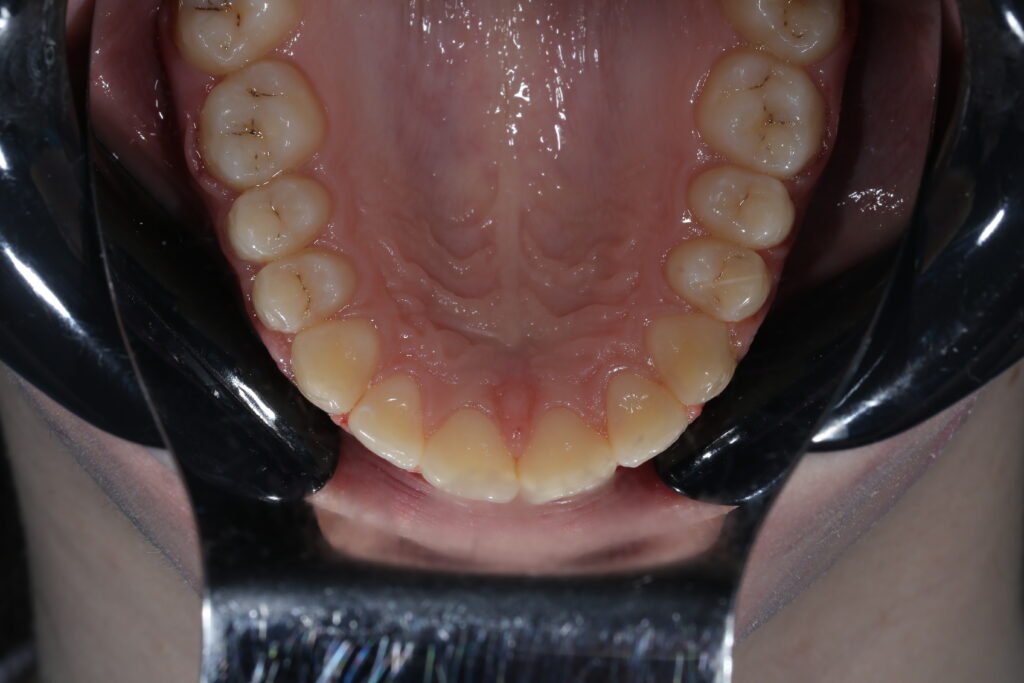

Ситуация до лечения

Диагноз: дистальный прикус, сужение, удлинение верхнего зубного ряда, скученность фронтальной группы зубов на нижней челюсти. Лечение проводилось самолигирующей брекет-системой Damon Q, срок лечения составил 2 года и 2 месяца.

Ситуация до лечения брекетами